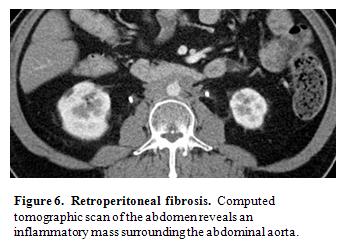

Chronic Periaortitis

Chronic periaortitis is now regarded as the umbrella term for inflammation in the retroperitoneum and peri-aortic regions that includes such entities as retroperitoneal fibrosis, inflammatory abdominal aortic aneurysm, and perianeurysmal fibrosis (39). IgG4-RD is now known to cause well over half of the cases previously regarded as “idiopathic” retroperitoneal fibrosis (Figure 6) (25, 73). When detected early, biopsies from patients with retroperitoneal fibrosis whose disease demonstrate histopathological and immunohistochemical features that are diagnostic of IgG4-RD (73). In contrast, biopsies performed in patients at a later phase of disease simply show fibrosis, because they represent a more advanced IgG4-RD stage in which the fibrotic features have become predominant. Nevertheless, the storiform morphology of the fibrosis can still be highly suggestive of IgG4-RD. In such cases, the IgG4/total IgG ratio within tissue rather than the number of IgG4-positive plasma cells/high-power field is often a key to recognizing IgG4-related retroperitoneal fibrosis (25).